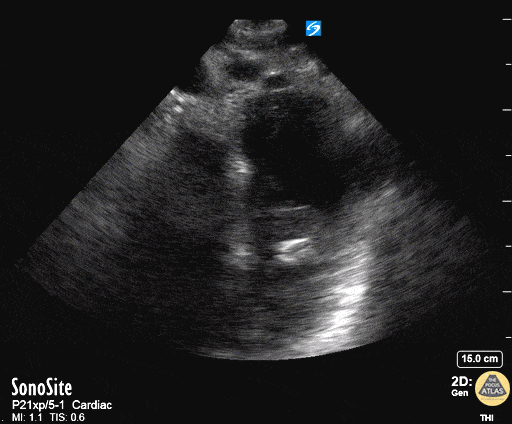

Thoracic Aortic Dissection & Aneurysm - Aortic Dissection On Suprasternal View

50 year old mandarin speaking man complains of vague central chest pain. You pursue a routine cardiac workup which is fairly normal. Upon discharging him, the nurse tells you his systolic in now in the 80's. After clenching the likely diagnosis of an Type A Aortic Dissection based on your echo, you confirm by placing the transducer in the patients suprasternal notch, transversely but with the probe marker rotated slightly toward the patient's hip and fan inferiorly. You see a grossly widened aorta and a dissection flap. Dr. Matthew Riscinti - Kings County Emergency Medicine, Dr. Benjamin Clearly - NYU Langone Emergency Medicine